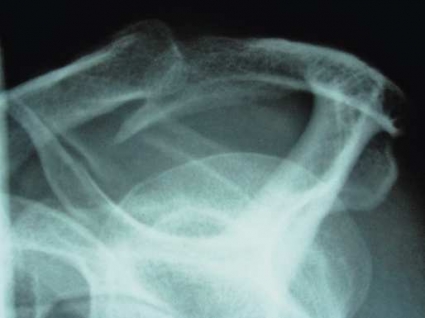

Att luxera sin axel är en synnerligen smärtsam och obehaglig upplevelse (Figur 3). Efter reposition återgår livet i regel snabbt till det normala, och åkomman kanske aldrig ger ytterligare besvär. Fortfarande diskuteras många frågor, exempelvis hur den primära luxationen hos yngre ska behandlas optimalt och vilka operationsmetoder som ska användas vid olika typer av instabilitet.